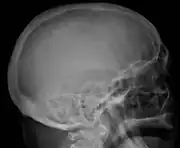

The diagnostic examination of a person with suspected multiple myeloma typically includes a skeletal survey. This is a series of X-rays of the skull, axial skeleton, and proximal long bones. Myeloma activity sometimes appears as "lytic lesions" (with local disappearance of normal bone due to resorption). And on the skull X-ray as "punched-out lesions" (pepper-pot skull). Lesions may also be sclerotic, which is seen as radiodense.[47] Overall, the radiodensity of myeloma is between −30 and 120 Hounsfield units (HU).[48] Magnetic resonance imaging is more sensitive than simple X-rays in the detection of lytic lesions, and may supersede a skeletal survey, especially when vertebral disease is suspected. Occasionally, a CT scan is performed to measure the size of soft-tissue plasmacytomas. Bone scans are typically not of any additional value in the workup of people with myeloma (no new bone formation; lytic lesions not well visualized on bone scan).

Bone pain affects almost 70% of people with multiple myeloma and is the most common symptom.[15] Myeloma bone pain usually involves the spine and ribs, and worsens with activity. Persistent, localized pain may indicate a pathological bone fracture. Involvement of the vertebrae may lead to spinal cord compression or kyphosis. Myeloma bone disease is due to the overexpression of receptor activator for nuclear factor κ B ligand (RANKL) by bone marrow stroma. RANKL activates osteoclasts, which resorb bone. The resultant bone lesions are lytic (cause breakdown) in nature, and are best seen in plain radiographs, which may show "punched-out" resorptive lesions (including the "raindrop" appearance of the skull on radiography). The breakdown of bone also leads to the release of calcium ions into the blood, leading to hypercalcemia and its associated symptoms.